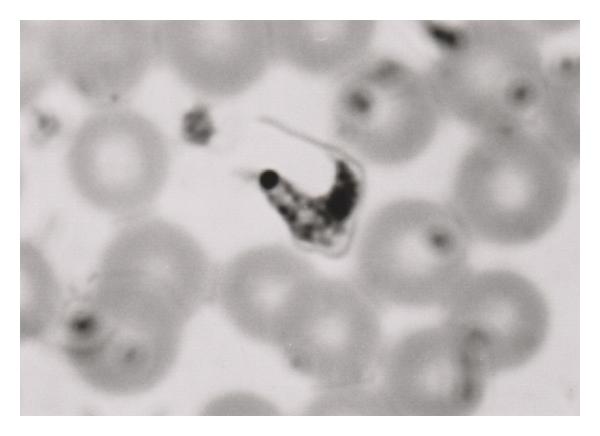

For many years, microscopy has been the only tool available for the detection of parasites through inspection of blood smears [10–14], tissue specimens [15–17], feces, lymph node aspirates [18, 19], bone marrow [20], and even cerebrospinal fluid [21]. However, sample preparation for direct observation is time-consuming, labour intensive, and proper diagnosis depends on qualified laboratory technicians. In the case of slide reading, a second independent reading is preferable, but not always required for accurate diagnosis. If need be, divided readings are resolved by a third reader. In endemic regions, where resources are limited, this proves to be difficult and misdiagnosis can significantly impact patient care. In reality, all major intestinal helminth infections are still solely dependent on microscopy for diagnosis. As for other parasite infections, many are confirmed by the use of microscopy in conjunction to other methods of diagnosis including serology-based assays and more recently molecular-based assays.